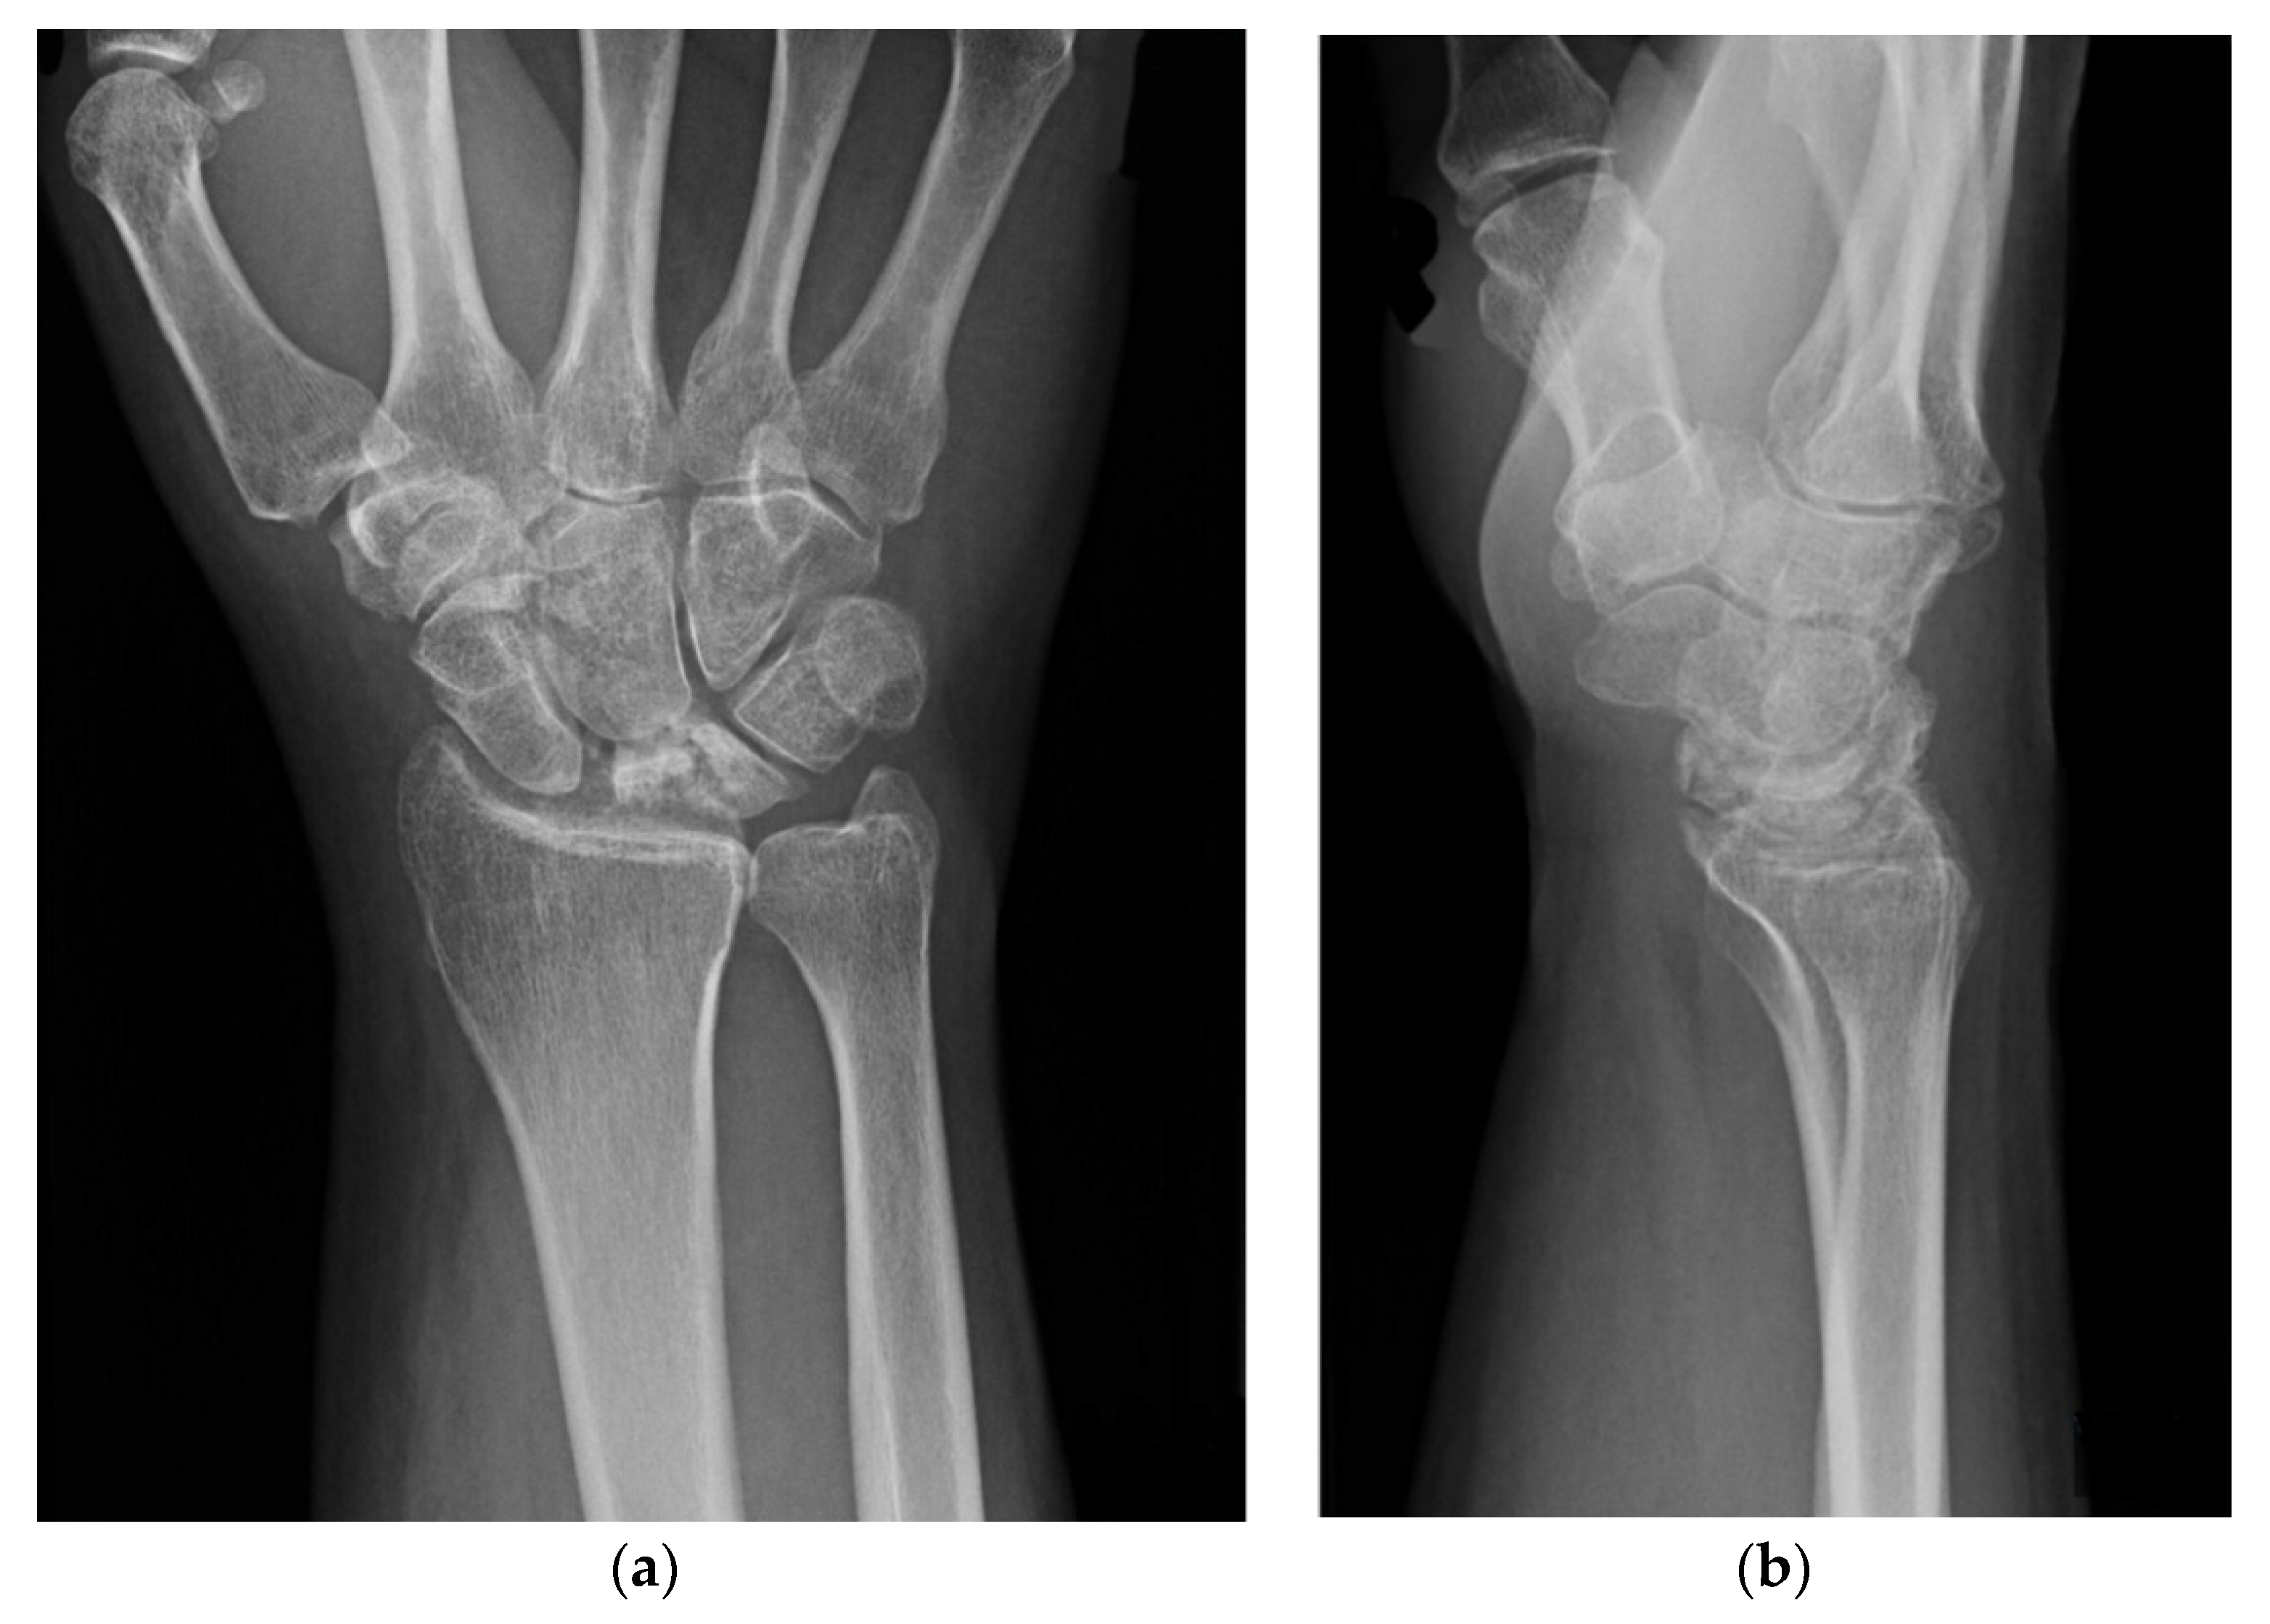

| Stage | Radiographs | MRI |

|---|---|---|

| I | Normal | ↓ T1 signal, lunate enhancement after contrast administration |

| II | Increased density without lunate collapse | ↓ T1 signal, variable T2 signal |

| IIIA | Lunate collapse, Radioscaphoid angle < 60° | ↓ T1 signal, variable T2 signal |

| IIIB | Lunate collapse with scaphoid palmar flexion (radioscaphoid angle > 60°) | ↓ T1 signal, variable T2 signal |

| IIIC | Lunate collapse with coronal lunate fracture (chronic) | ↓ T1 signal, variable T2 signal |

| IV | Lunate collapse with radiocarpal or midcarpal degenerative arthritis | ↓ T1 signal, variable T2 signal |